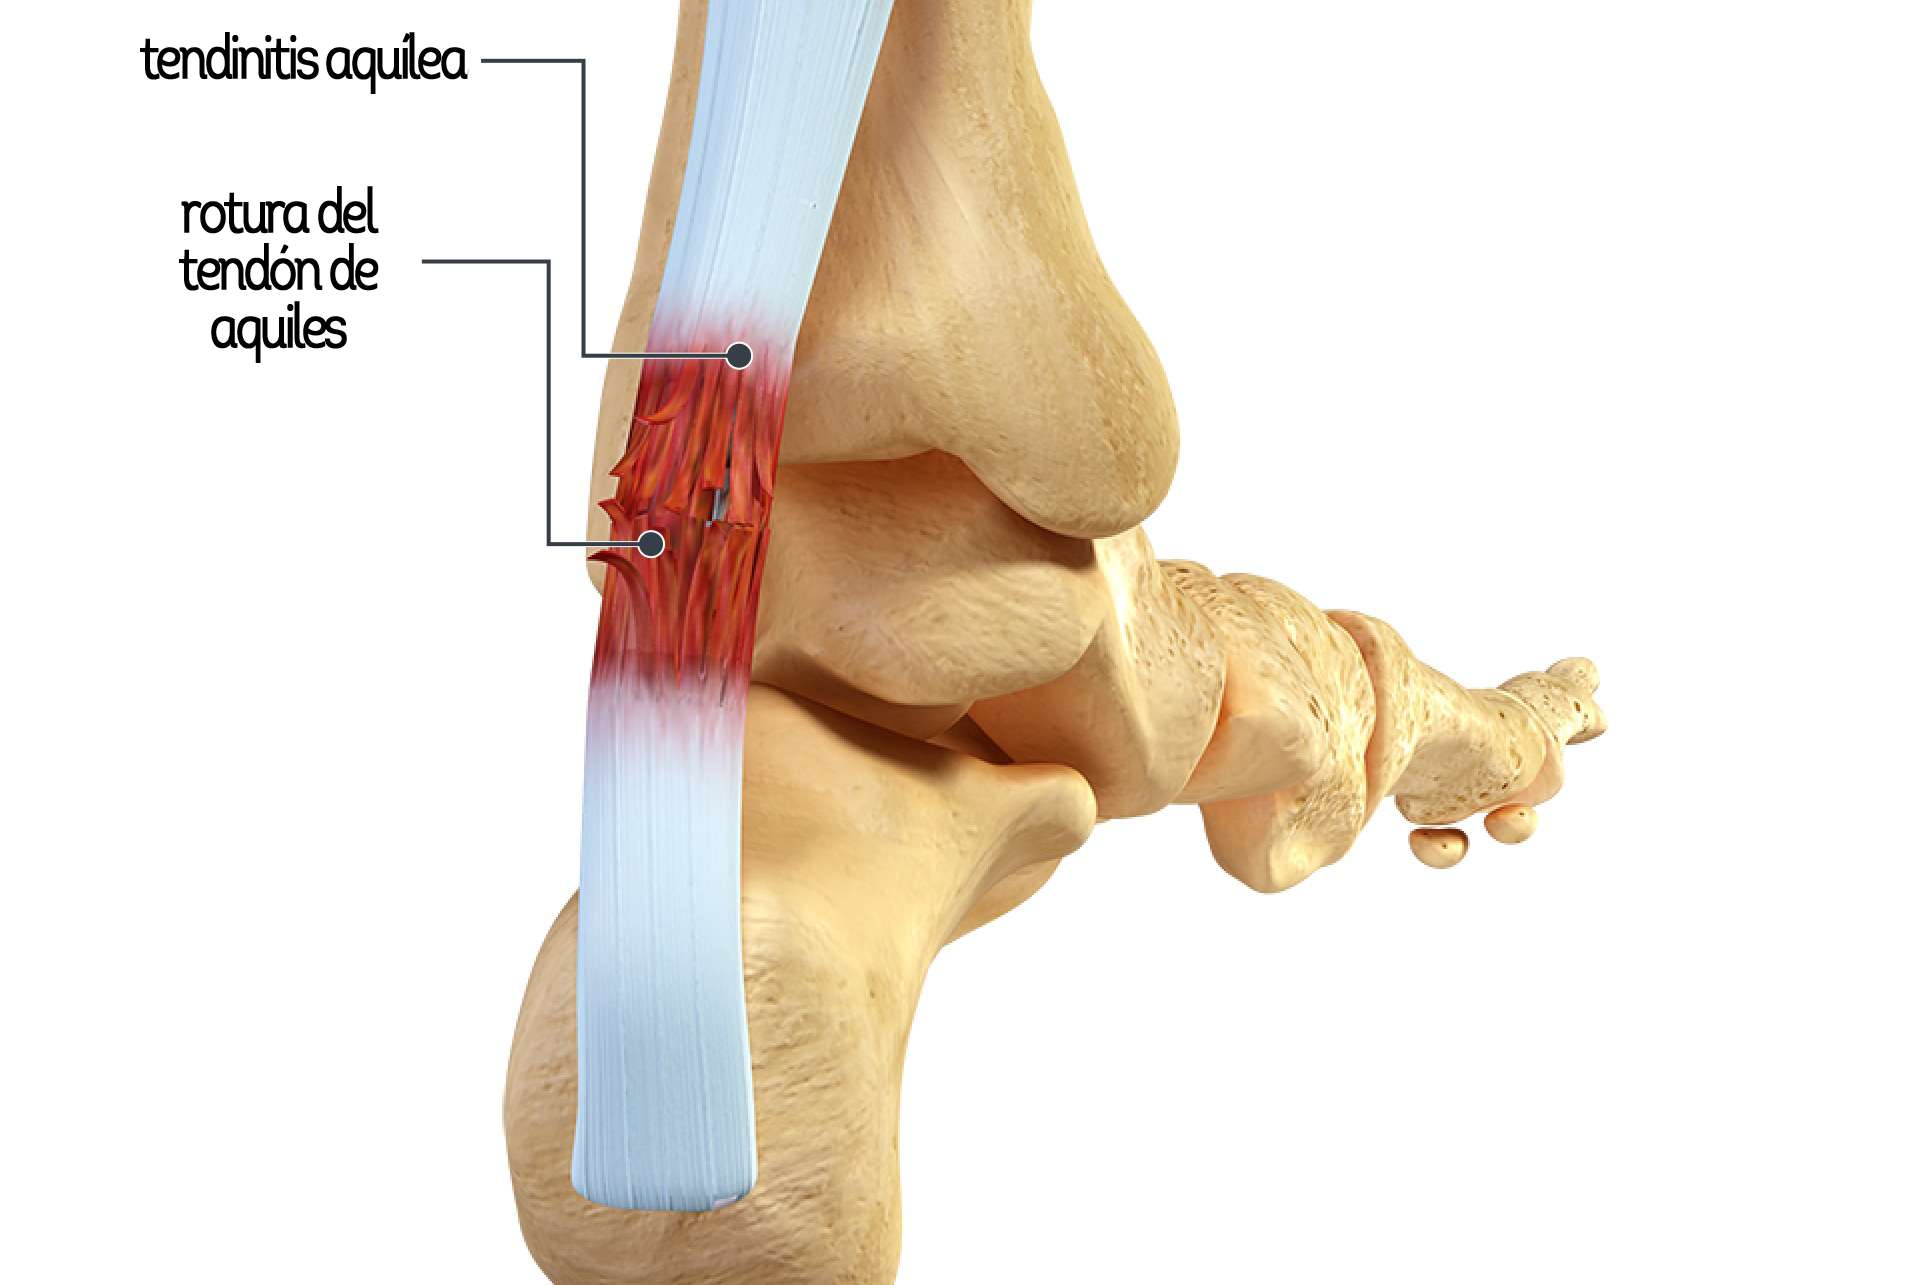

WebLas calcificaciones son muy frecuentes, aunque no siempre son la causa del dolor ya que a veces pueden provenir de la propia inflamación que genera esa calcificación. WebEl tendón de Aquiles o también llamado tendón calcáneo, es un tejido fuerte y resistente de la parte posterior e inferior del miembro inferior que sale de la unión de varios músculos. WebLas principales causas de las calcificaciones en el tendón de Aquiles son: “Una tendinitis/tendinopatia crónica mal curada, un sobreuso y microtraumatismos. WebEl tendón de Aquiles es el encargado de propulsarnos al caminar, correr o saltar. Los tendones son estructuras que unen el músculo al hueso, y el tendón de. WebLa tendinopatía calcificada insercional del tendón de Aquiles (ACIT) es una afección causada por el deterioro del tendón de Aquiles en el talón, que da lugar a. WebCALCIFICACIONES EN EL TENDÓN DE AQUILES. Prentamos el caso clínico de una paciente mujer de 53 años que acudió a nuestra consulta con dolor en el talón derecho. WebEn nuestro estudio hemos detectado radiológicamente (radiografía lateral de rodillas) calcificaciones de los tendones gastrocnemios en el 27,7% de las rodillas evaluadas, lo. WebTratamiento calcificación tendón de aquiles con ondas de choque. Hoy os mostramos un vídeo del tratamiento satisfactorio aplicado a un paciente con una.

WebLas calcificaciones son un desorden caracterizado por la deposición de cristales de calcio que endurecen un tejido elástico como tendones.